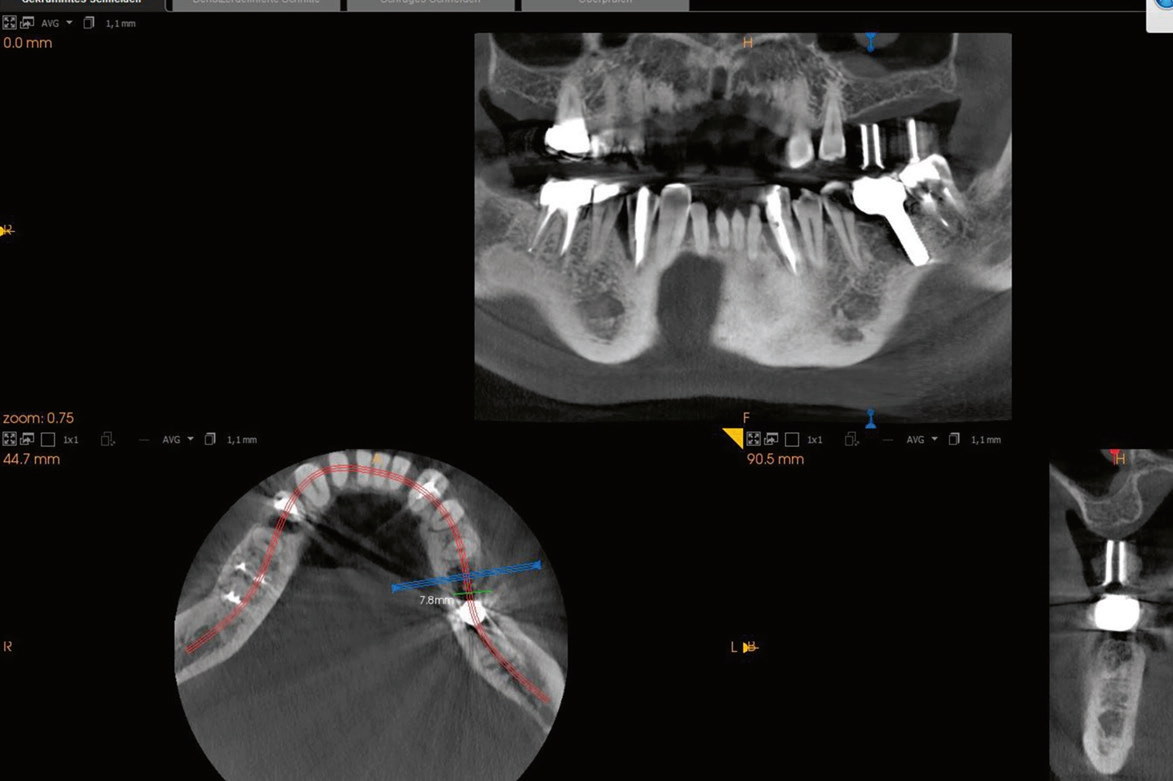

60-jähriger, männlicher Patient mit seit etwa acht Jahren bestehender Freiendsituation in regio 26/27. Drei Jahre zuvor wurde auf Position 36 ein PURE Monotype erfolgreich eingesetzt und prothetisch versorgt. Insgesamt ausgezeichnete Mundhygiene und absolut reizfreie Situation an 36. Der Wunsch des Patienten war nun die Versorgung der Position 26 mittels eines Keramikimplantates ohne größere chirurgische Intervention. Nach Anfertigung der dreidimensionalen Aufnahme (DVT) stellten sich ein ausreichendes transversales Knochenangebot und eine vertikale Höhe von ca. 5 – 6 mm zur Kieferhöhle dar, so dass ein interner Sinuslift und die Verwendung eines zweiteiligen Implantates geplant wurden. Das geringe vertikale Knochenangebot und die reduzierte Qualität verglichen mit dem Unterkiefer hätten bei Verwendung eines einteiligen Implantates mit transgingivaler Heilung ein Risiko für die erfolgreiche Osseointegration dargestellt. Zur Vorbereitung wurde die leichte basale Schleimhautschwellung beim Hals-Nasen-Ohren Arzt abgeklärt und der Patient führte täglich Nasenspülungen durch.